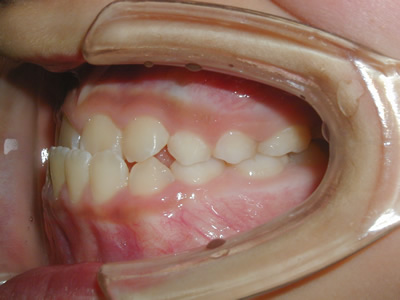

永久歯に交換するためのスペース不足による前歯のガタガタで、取り外しができる拡大床にて上下顎の幅を拡大した後、上顎の前歯をマルチブラケット装置で並べました。治療の期間は1年9か月でした。

初診時